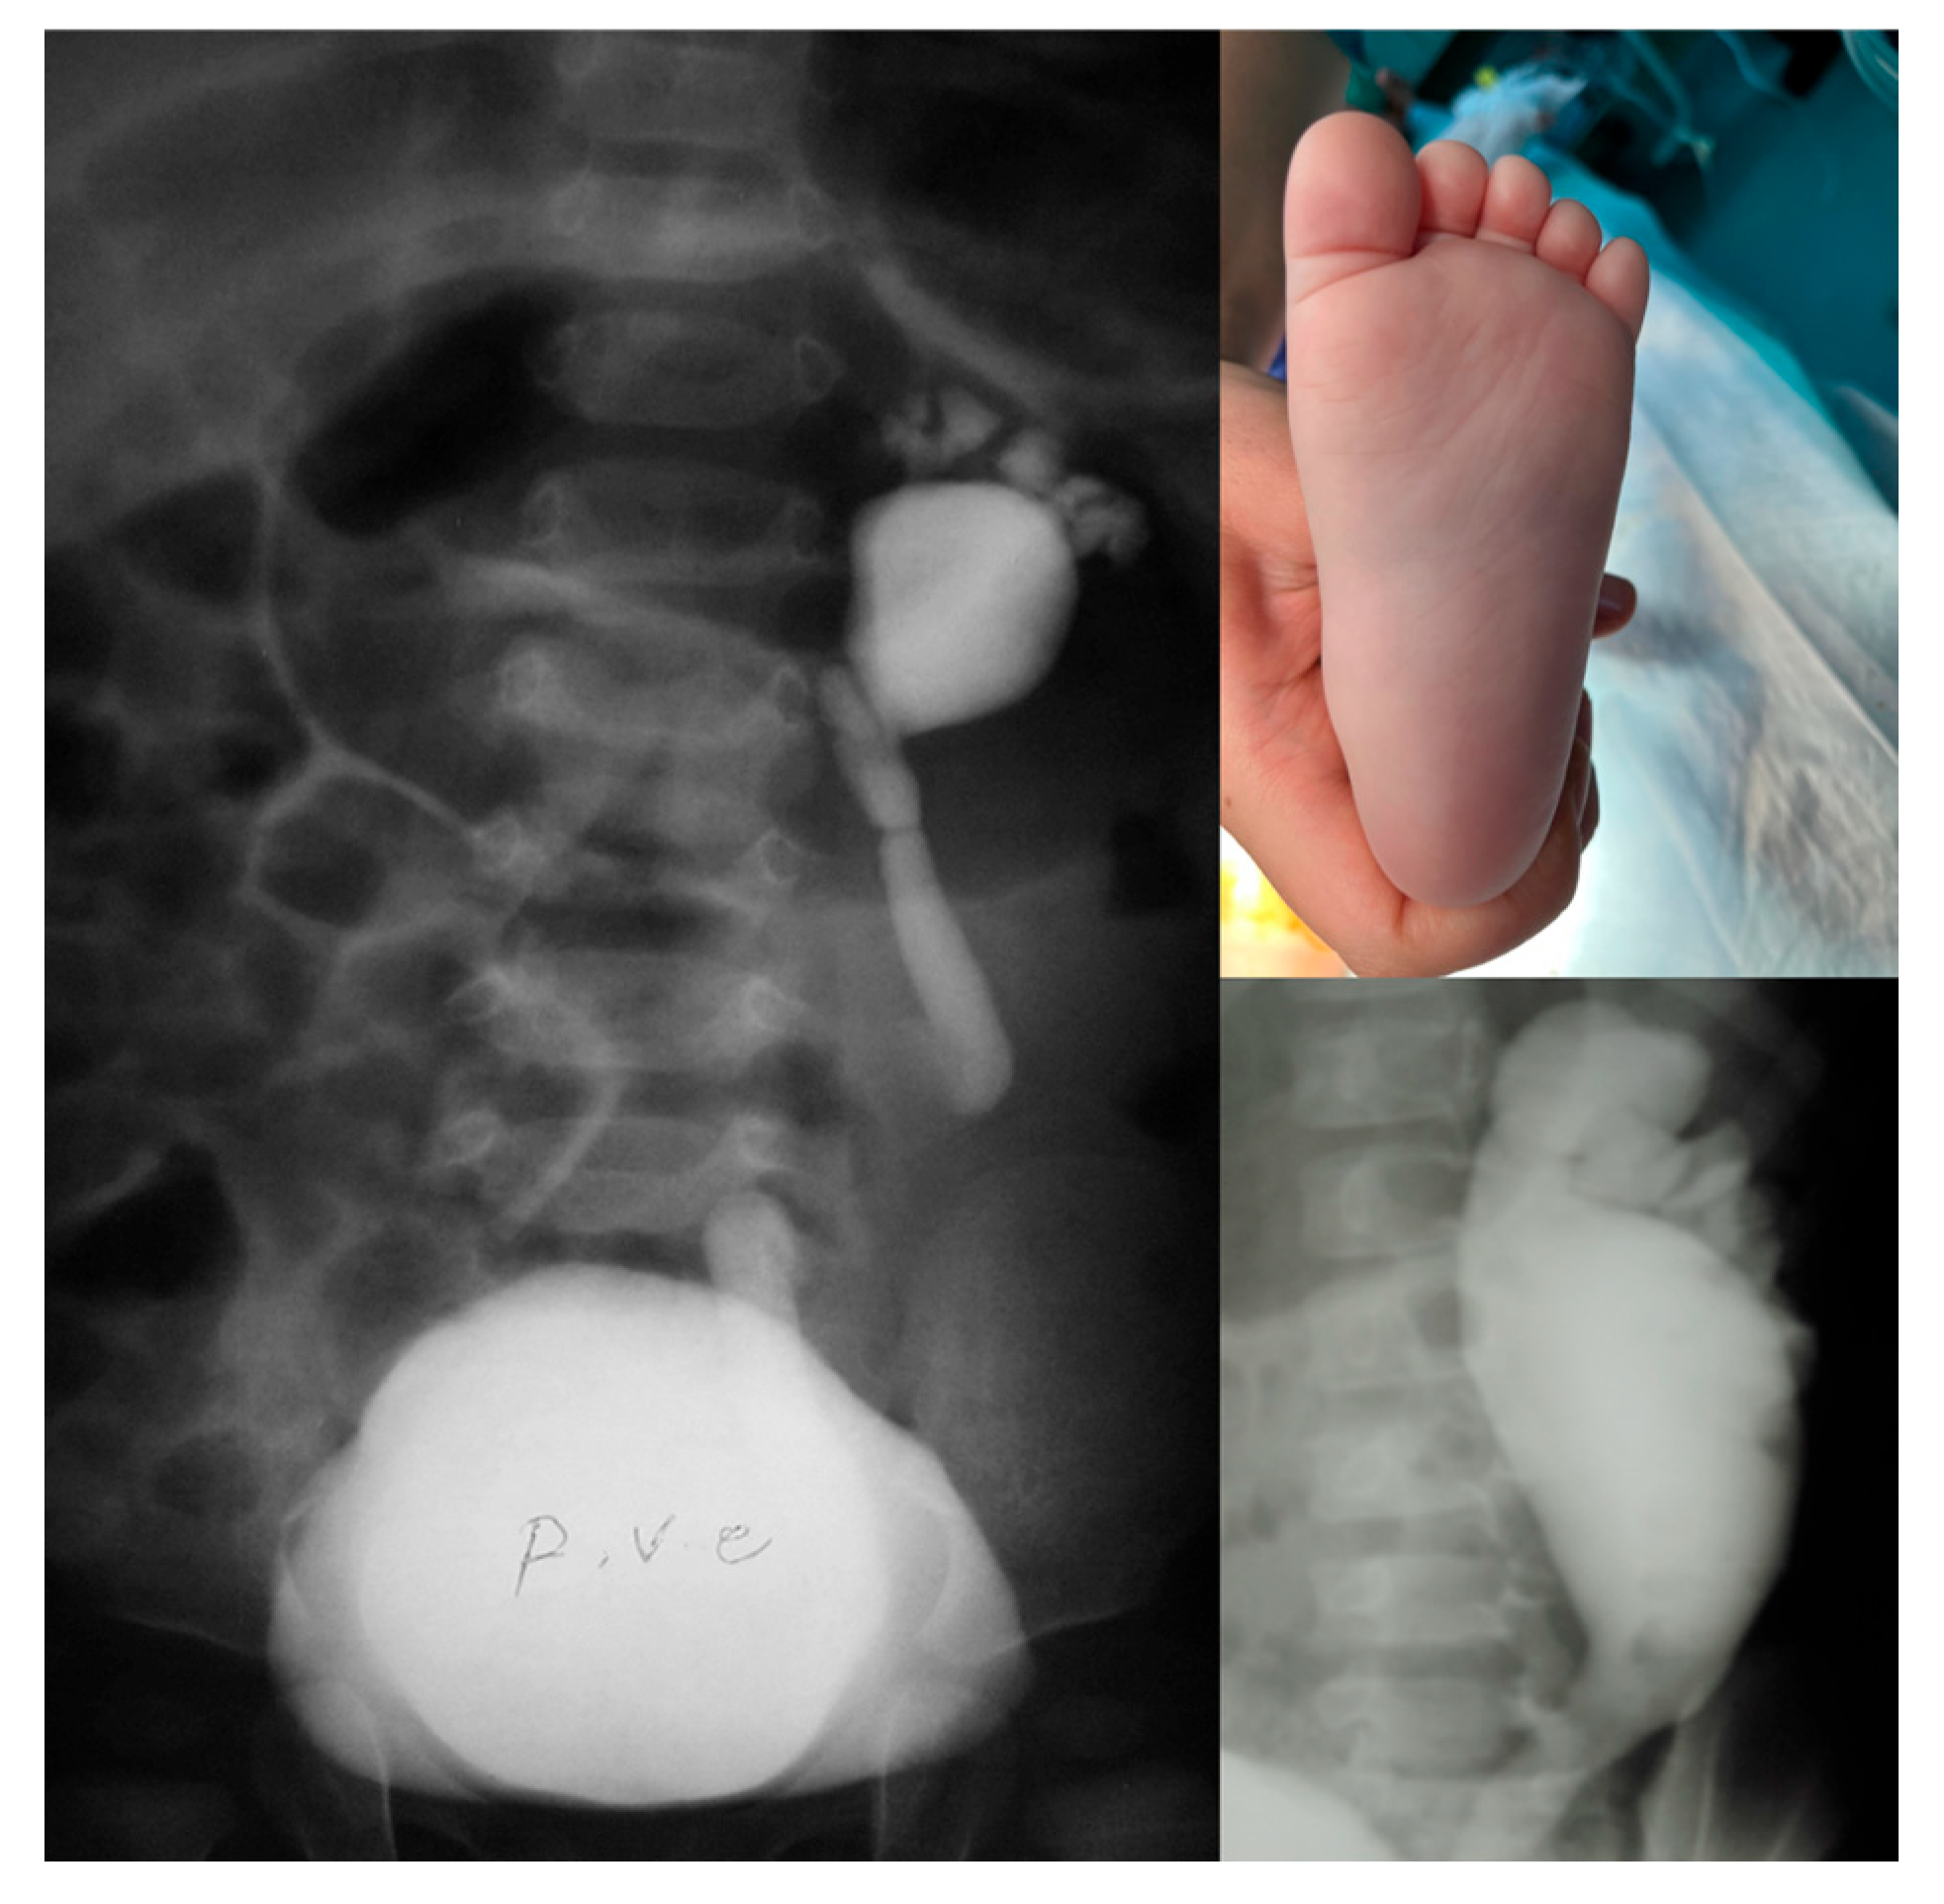

Medical records of individuals diagnosed with VUR from 2007 to 2019 were retrospectively reviewed. For each patient, demographic and clinical information, VCUG and Tc99m dimercaptosuccinic acid (Tc99m-DMSA) scintigraphy results, and VUR grading based on the standards set by the International Reflux Study in Children were extracted. Inclusion criteria included the presence of either a “footprint” sign or high-grade VUR (grade IV or V) in VCUG, as indicated in radiology reports and pediatric urologist notes. The “footprint” sign was characterized as dysmorphic calyces connected to a dilated renal pelvis, forming a distinct “footprint” shadow shape, depicted in Figure 1. While no quantitative measurements (e.g., calyceal angle or pelvis ratios) were performed in this study, we based our visual identification on previously published radiological definitions. Martin et al. [7] described the sign as a superior migration of the calyceal axis with an inferior displacement and increased filling of the renal pelvis, producing a “flowerpot” configuration. They also reported that during maximal reflux, calyces are located largely cephalad to the renal pelvis rather than lateral, with a significantly greater median calyceal-spine angle (52° [range 37–66]) in affected kidneys compared to high-grade controls (13° [range 2–37]). These quantitative measures support the visual criteria used to identify the footprint sign. VCUG images were first reviewed by two experienced pediatric radiologists, and the presence of the “footprint” sign was subsequently confirmed by a senior pediatric urologist. Exclusion criteria encompassed individuals with a single kidney, multicystic dysplastic kidney, prune-belly syndrome, duplex collecting system, renal ectopia, posterior urethral valve (PUV), or those lacking a Tc99m-DMSA scan.

Figure 1.

Dysmorphic calyces attached to a dilated renal pelvis form a distinct “footprint” shadow shape.